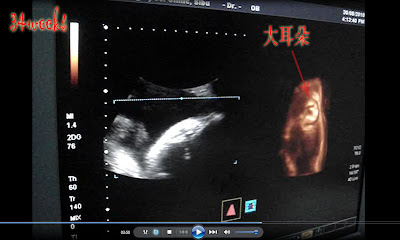

34周的点点好大了哦 =)

就一直告诉点点说,千千万万别再用手遮脸蛋了,别再让我失望而归~

一个月多没看到TA的脸了,超想念的。

这小亲爱果真有听话 ^^

现在来看看有趣的B超录影截图吧!.

【34周的B超单数据】双顶径(BPD) 89.6mm (偏大好多啊@@)股骨长(FL) 61mm腹围面积 (FTA) 65.33cm2点点的重量估计 2308g.

医生说点点比普通的宝宝

偏大两周。

两个星期内,

TA体重增加了将近500g,点点很棒!

现在的比例是ok,但希望点点的头别太大!很难生也~

紧张的

4D scan来了。多怕这顽皮点不合作。

很明显的,点点太大了,根本照不到什么了。

只能focus在TA的脸~

动来动去~这回可让我看到大耳朵了吧 =P